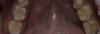

Art 7 Опубликовано 12 апреля, 2013 Поделиться Опубликовано 12 апреля, 2013 ситуация допрепарирование и оттиски были сделаны раздельно для каждой стороны3,6 и 3,74,6 и 4,7и готовая работа фиксировалась в одно посещение 4 Ссылка на комментарий

johniola Опубликовано 12 апреля, 2013 Поделиться Опубликовано 12 апреля, 2013 что?, что? вы про что?)это вкладки? 1 Ссылка на комментарий

Art 7 Опубликовано 12 апреля, 2013 Автор Поделиться Опубликовано 12 апреля, 2013 это вкладки?Да Ссылка на комментарий

Art 7 Опубликовано 12 апреля, 2013 Автор Поделиться Опубликовано 12 апреля, 2013 Скажите из чего вкладки? Правда что ль золото? Что- то не похоже, может я и не права, но напоминает амальгаму у меня аж дежавю какое- то случилось . Хотя врачебная работа гуд..!Вкладки из золота. Правда правда честно честно Ссылка на комментарий

Art 7 Опубликовано 12 апреля, 2013 Автор Поделиться Опубликовано 12 апреля, 2013 Золотые вклади - иницатива пациента или ваша?Моя Ссылка на комментарий

Art 7 Опубликовано 12 апреля, 2013 Автор Поделиться Опубликовано 12 апреля, 2013 Артур, почему в данном клиническом случае отдано предпочтение металлическим вкладкам?Иван, золото это вечная пломба. Если смогу найти губчатое золото то можно сделать кучу шикарных кейсов. Ссылка на комментарий